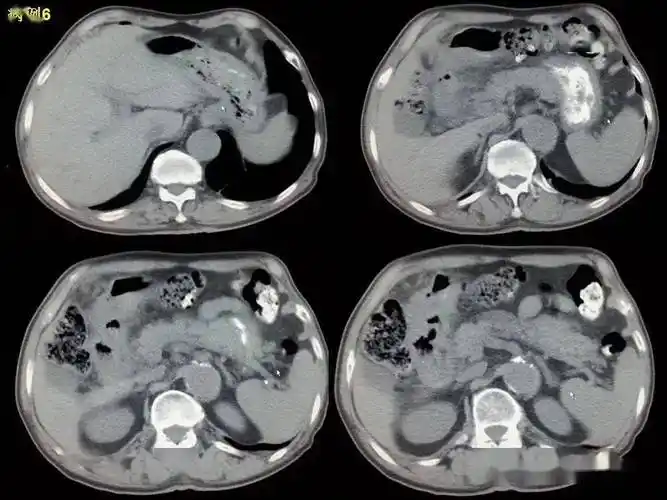

消化道穿孔ct影像大汇总看完印象深刻

(1) 腹部ct:膈下多发游离气体,考虑胃窦部穿孔机会大.辅助检查t:38.

炎体征明显,急诊全腹部平扫示:腹腔内多发游离气体,胃窦部胃壁稍增厚